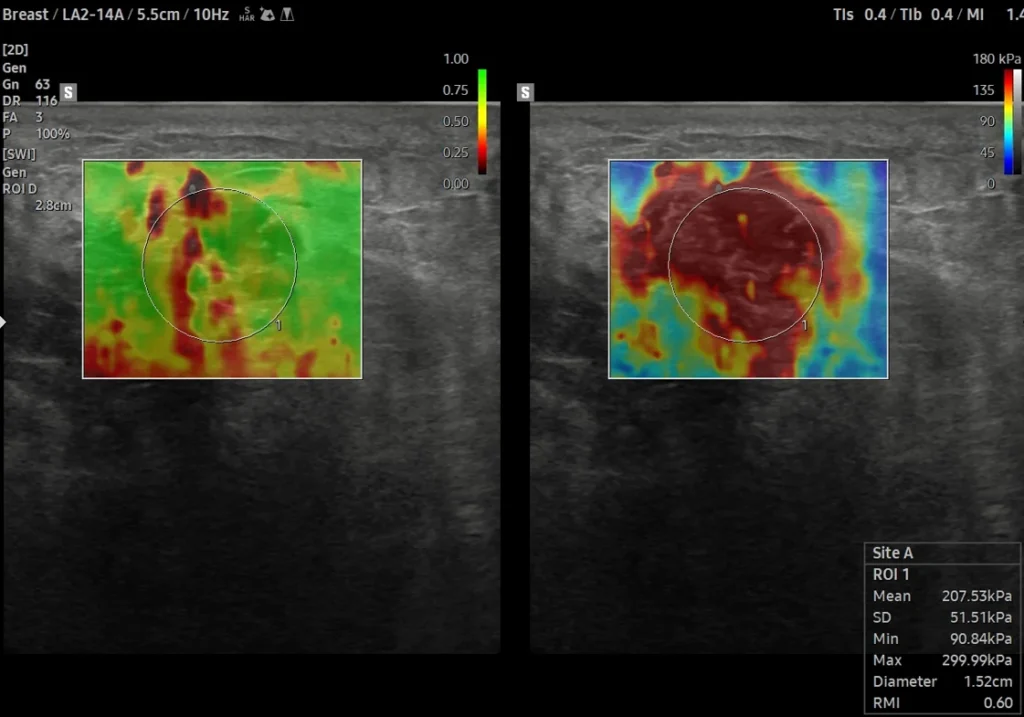

The ultrasound system evaluates how much the breast tissue compresses or moves in response to gentle pressure (or shear waves).

• Soft tissue = likely benign

• Hard/stiff tissue = needs further evaluation

A color-coded stiffness map is added to your ultrasound images for more precise evaluation.

• High-resolution ultrasound with Shear Wave Elastography